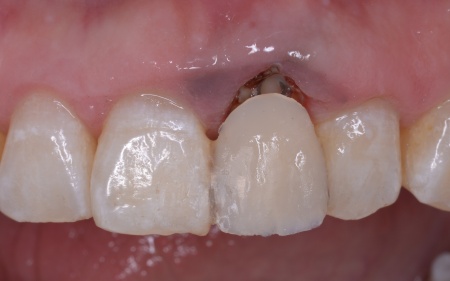

拝見したところ、左上前歯(中切歯)は被せ物で治療が施されていたものの、歯と歯茎の境目がほかの歯よりも上方にあり、歯が長く見えています。

まずは左上前歯にエクストリュージョンを行い、歯と歯茎の境目を整えたうえで抜歯を行います。抜歯と同時にインプラントを埋め込み、治療中の審美性を考慮して仮歯を装着しました。